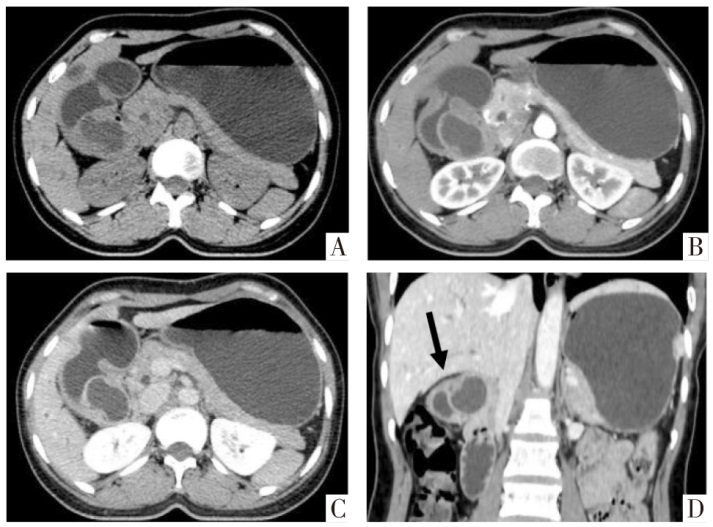

腹部平扫及增强CT影像。A-C图分别为平扫、动脉期和静脉期横断面影像。D图为静脉期冠状面影像,箭头示“脐凹征”。